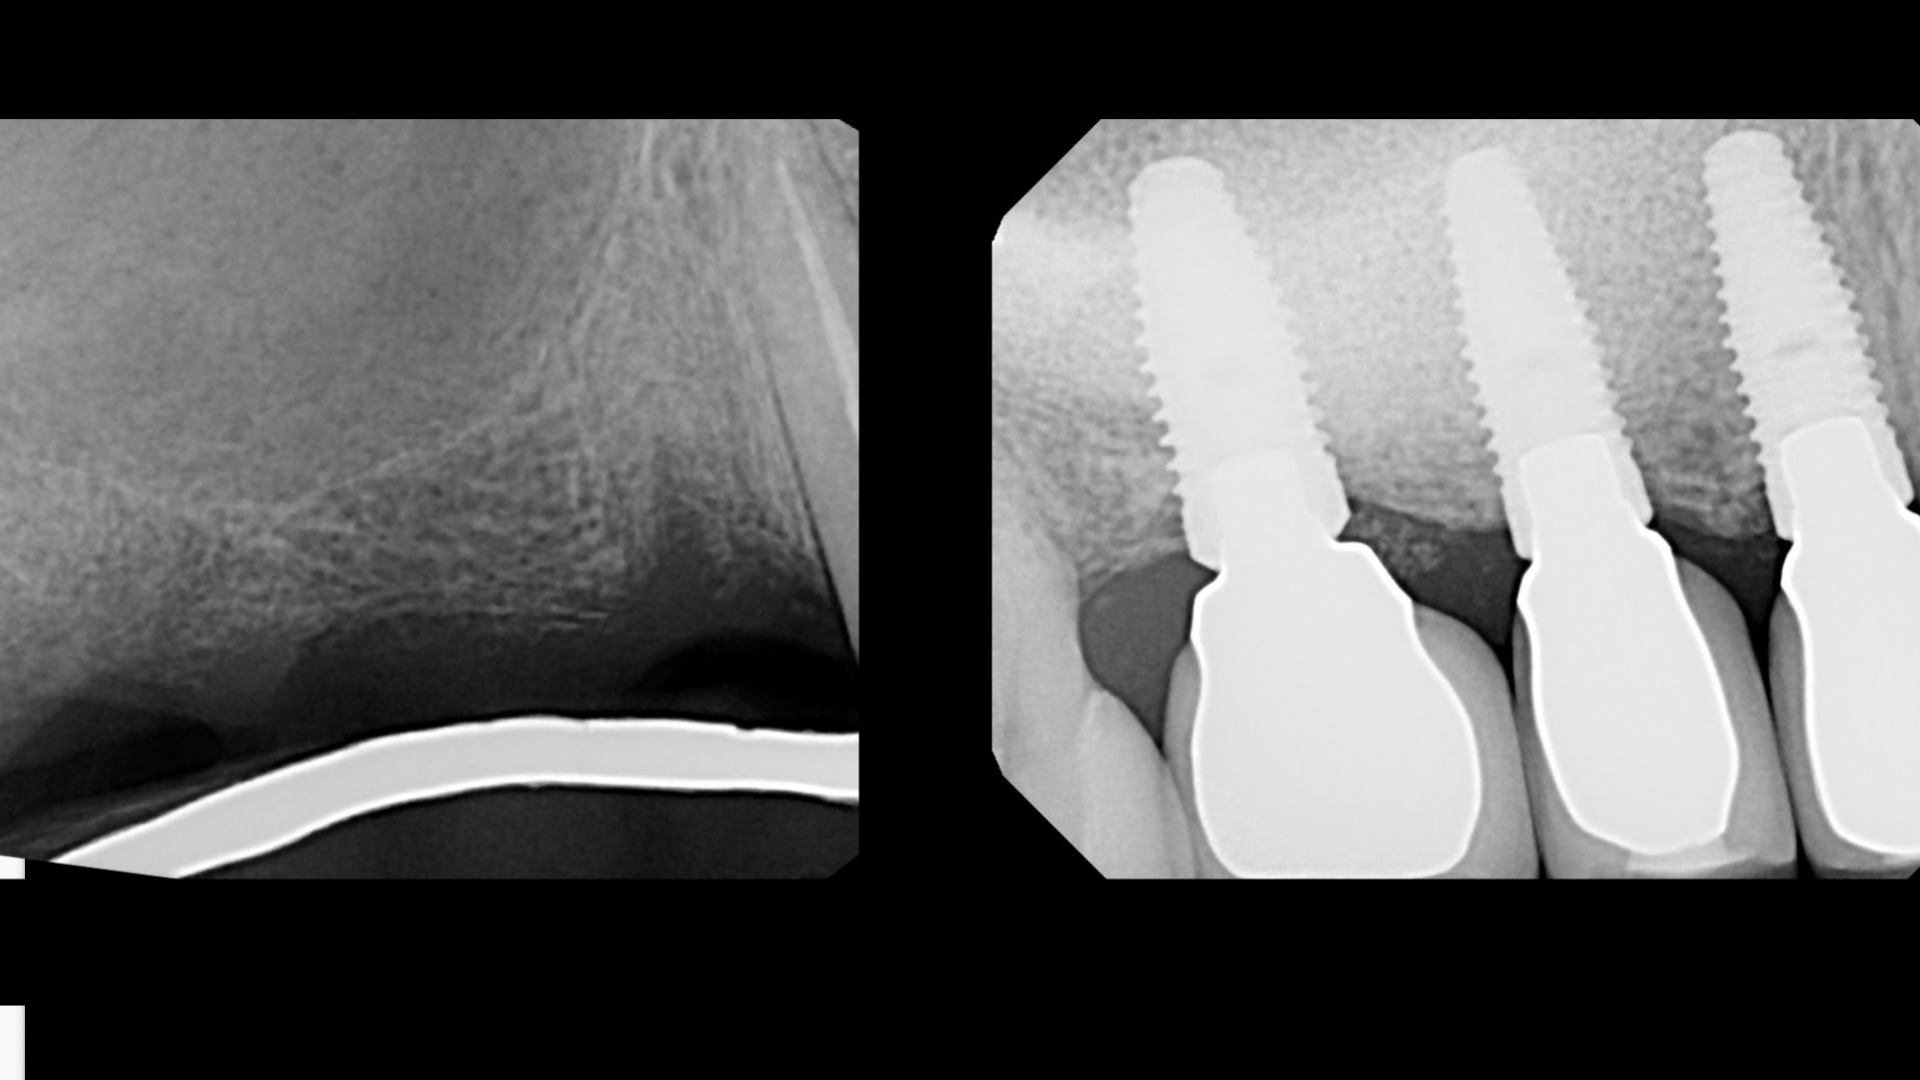

Thank you for signing up for the Implant & Sinus Lift Training Webinar!